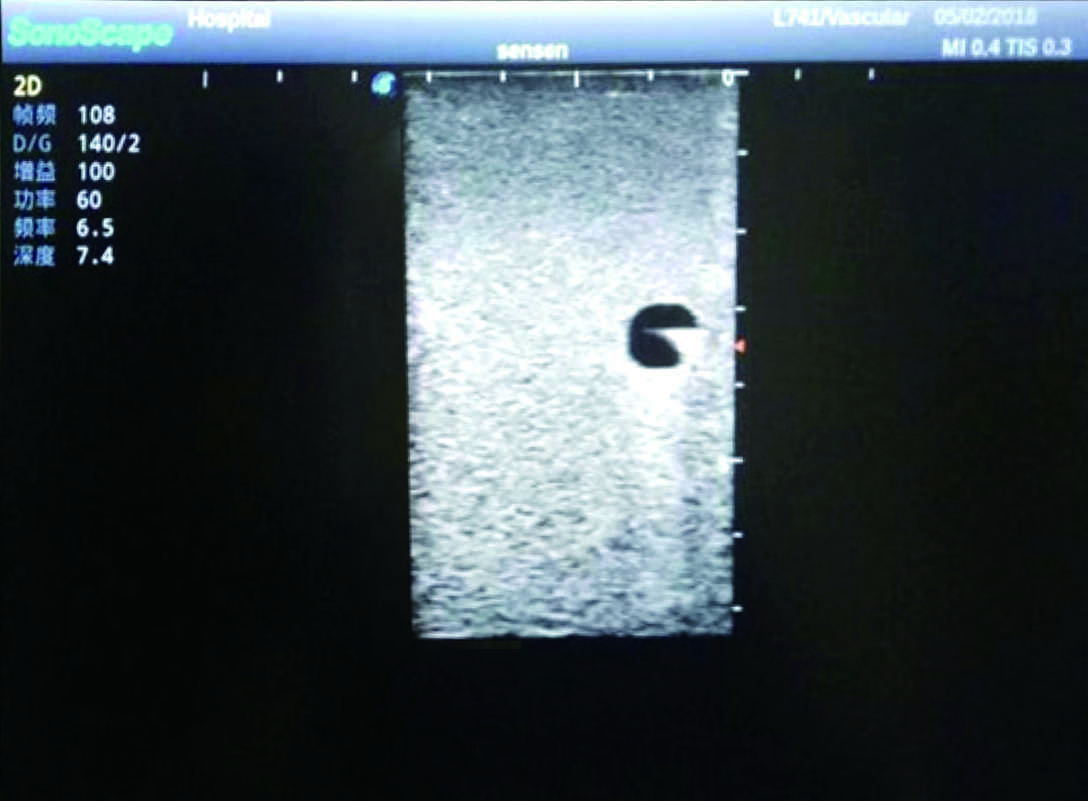

Product size(mm) 700×500×160

It is a model covering up from lobulus auriculae plane to the umbilical plane, and it has anatomical structures like clavicle, rib, sternocleidomastoid, jugular vein and basilic vein.

1)   Made of high molecular polymer ultrasound material, close to the real skin

2)   It can be used by real ultrasound machines

3)   Clear and real images of the tissues and organs (basilic vein and superior vena cava)